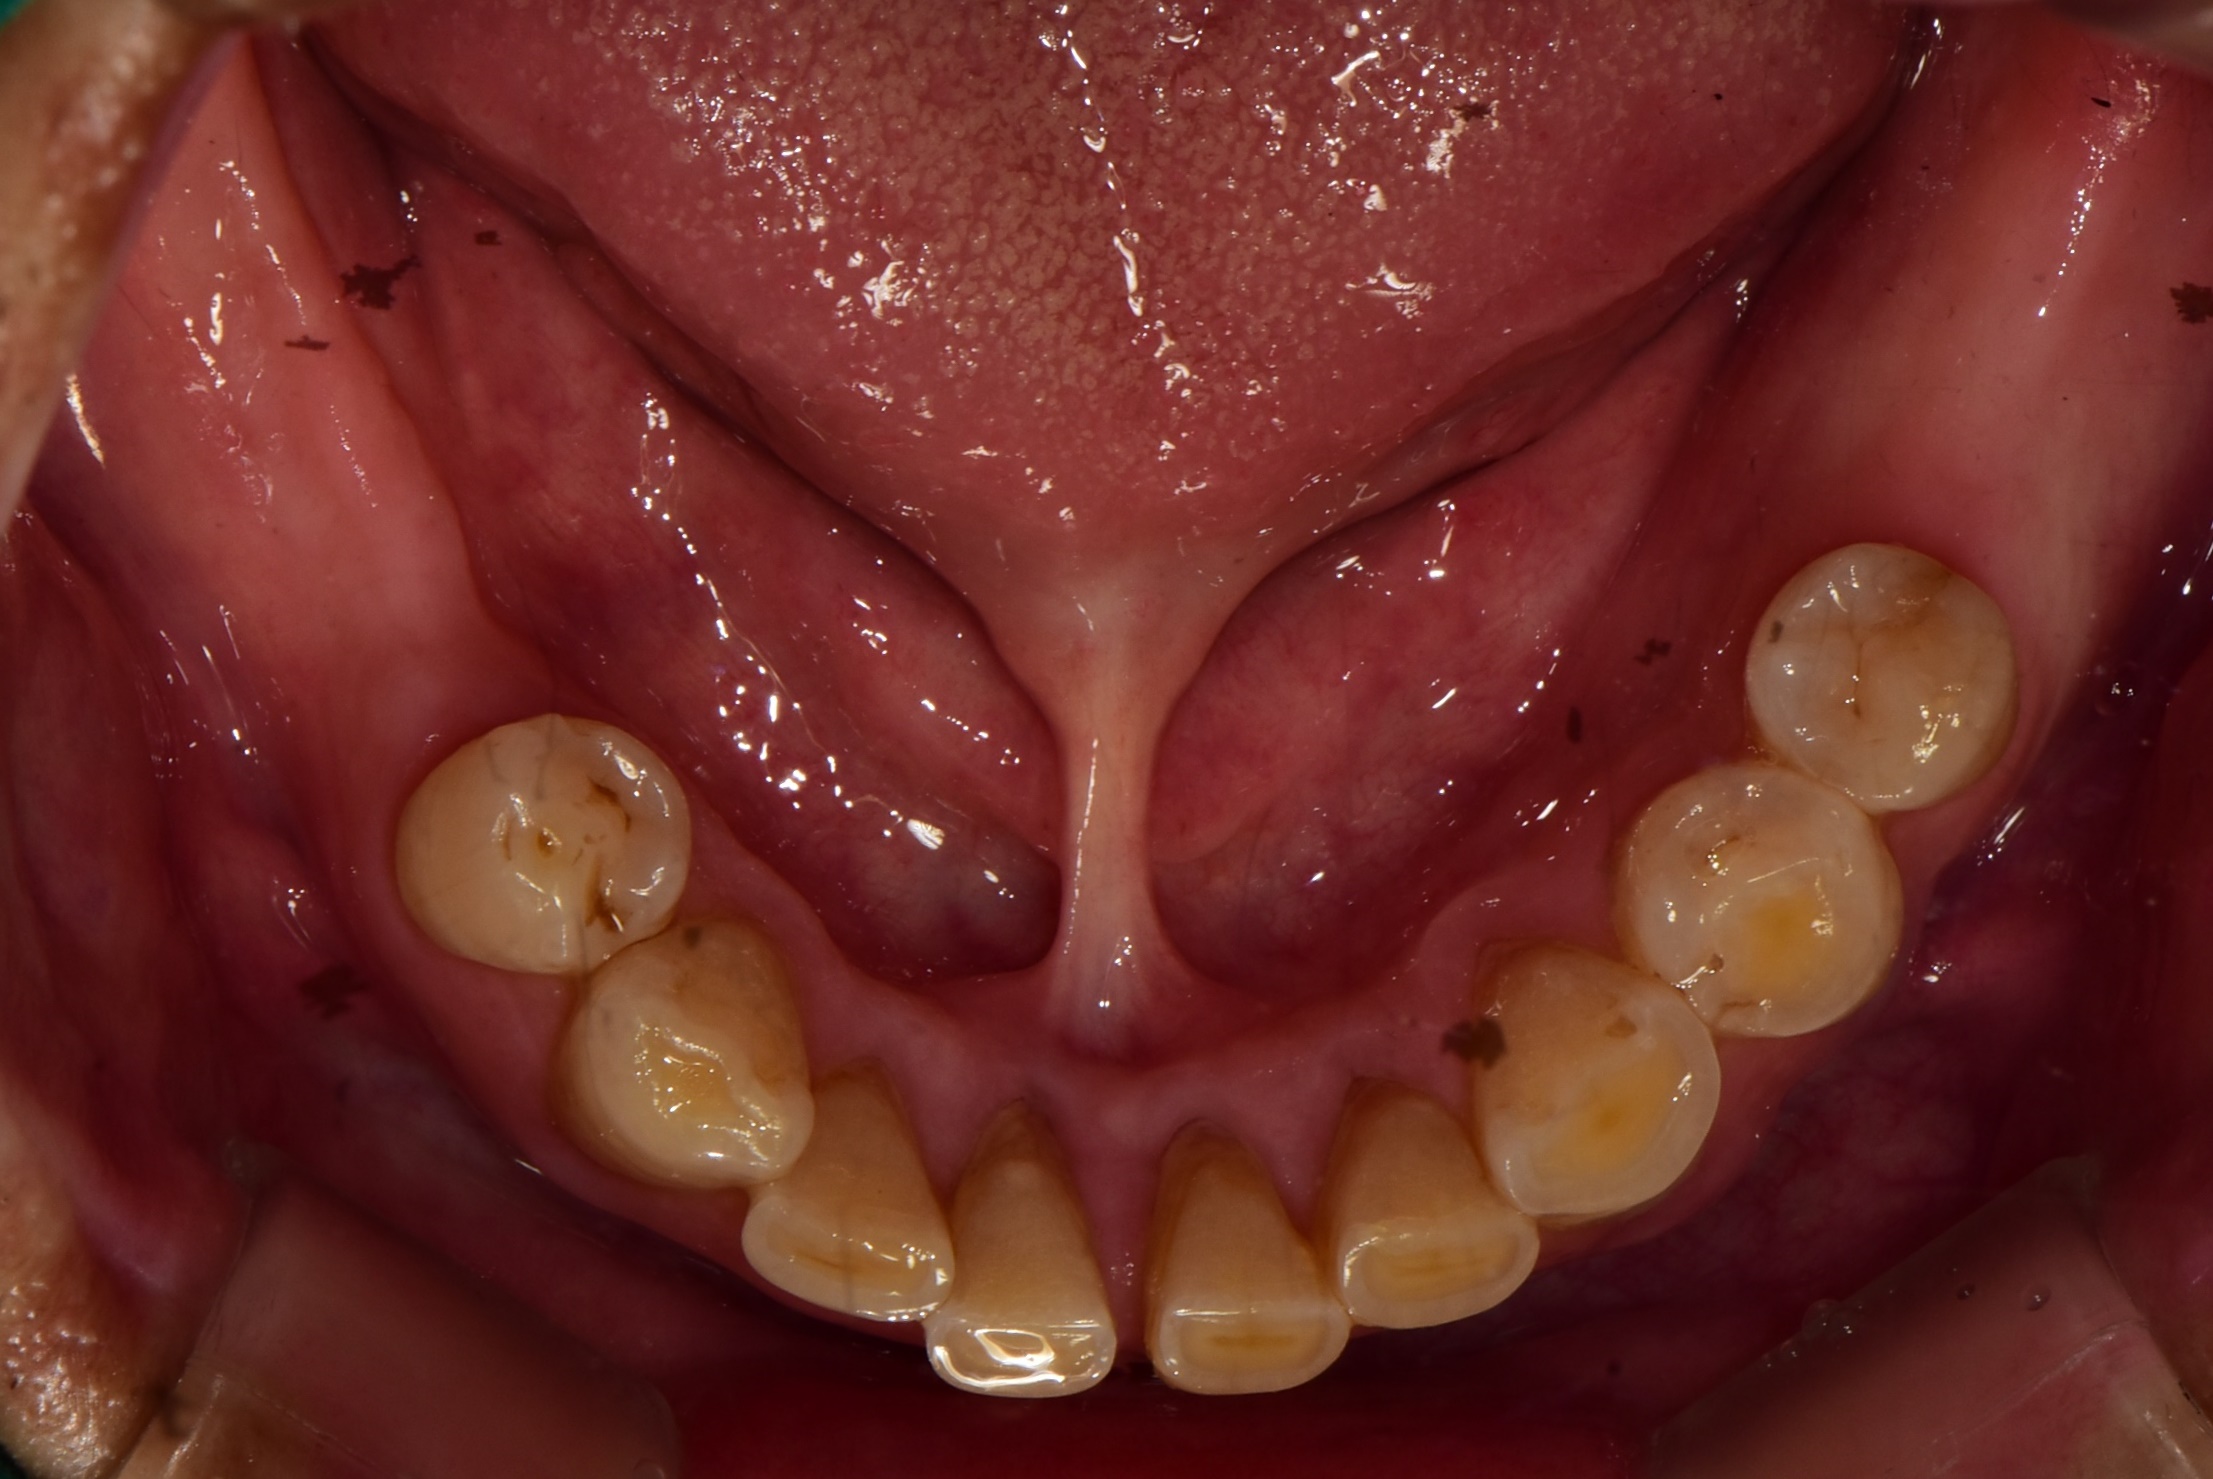

오랜기간 어금니가 없이 지내셨던 60대 남성분의 치료 사례입니다.

처음 김포 치과에 내원하셨을 당시 위에는 송곳니 하나를 제외하고는 다 흔들리고 어금니는 빠진지 오랜된 상태였습니다.

<치료 전>